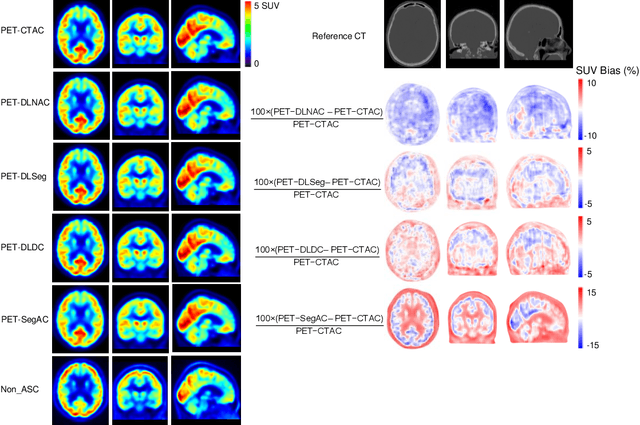

Abstract:Attenuation and scatter correction (AC) is crucial for quantitative Positron Emission Tomography (PET) imaging. Recently, direct application of AC in the image domain using deep learning approaches has been proposed for the hybrid PET/MR and dedicated PET systems that lack accompanying transmission or anatomical imaging. This study set out to investigate deep learning-based AC in the image domain using different input settings.